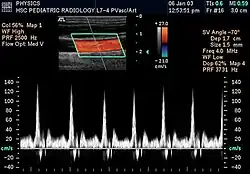

O ultrassom Doppler, ou simplesmente eco-Doppler, é um tipo de ultrassom que utiliza o ultrassom e o efeito Doppler para avaliar as ondas de velocidade de fluxo de certas estruturas do corpo, geralmente vasos sanguíneos, que são inacessíveis à visão direta.[1] A técnica permite determinar se o fluxo se dirige para a sonda ou se se afasta dela, bem como a velocidade relativa desse fluxo. Calculando a variação da frequência do volume de uma amostra específica, por exemplo, o fluxo sanguíneo numa válvula cardíaca, a sua velocidade e direção podem ser determinadas e visualizadas. A impressão de um ultrassom tradicional combinado com um ultrassom Doppler é conhecida como ultrassom duplex.[2]

A informação Doppler é representada graficamente com um Doppler espectral, ou como uma imagem utilizando Doppler direcional ou Doppler de potência (Doppler não direcional). A frequência Doppler enquadra-se na gama audível e é representada por altifalantes estéreo, produzindo um som pulsante distinto, embora sintético.

O Doppler colorido é essencialmente o sistema informático integrado no aparelho de ultrassons. Atribui unidades de cor dependendo da velocidade e direção do fluxo sanguíneo. Por convenção, o vermelho é atribuído ao fluxo em direção ao transdutor e o azul ao fluxo em direção oposta.

A maioria dos aparelhos modernos utiliza ultrassons Doppler pulsados, produzindo um Doppler de fluxo colorido, para medir o fluxo no centro ou na periferia de um vaso sanguíneo.[3] Os dispositivos de onda pulsada transmitem e recebem uma série de impulsos, recebendo geralmente a informação antes de enviar o próximo. A variação da frequência de cada pulso é ignorada, mas as variações de fase relativas dos pulsos são utilizadas para obter a variação da frequência, uma vez que a frequência é a taxa de variação dessa fase. A principal vantagem do Doppler pulsado em relação à variedade de onda contínua é que a informação da distância é obtida (o tempo entre a transmissão e a recepção dos impulsos pode ser convertido em distância, conhecendo-se a velocidade do som). A desvantagem do Doppler pulsado é que as medições podem sofrer aliasing. O termo "ecografia Doppler" ou "sonografia Doppler" tem sido aceite para se referir às versões pulsada e contínua, apesar dos diferentes mecanismos pelos quais cada uma mede o fluxo.